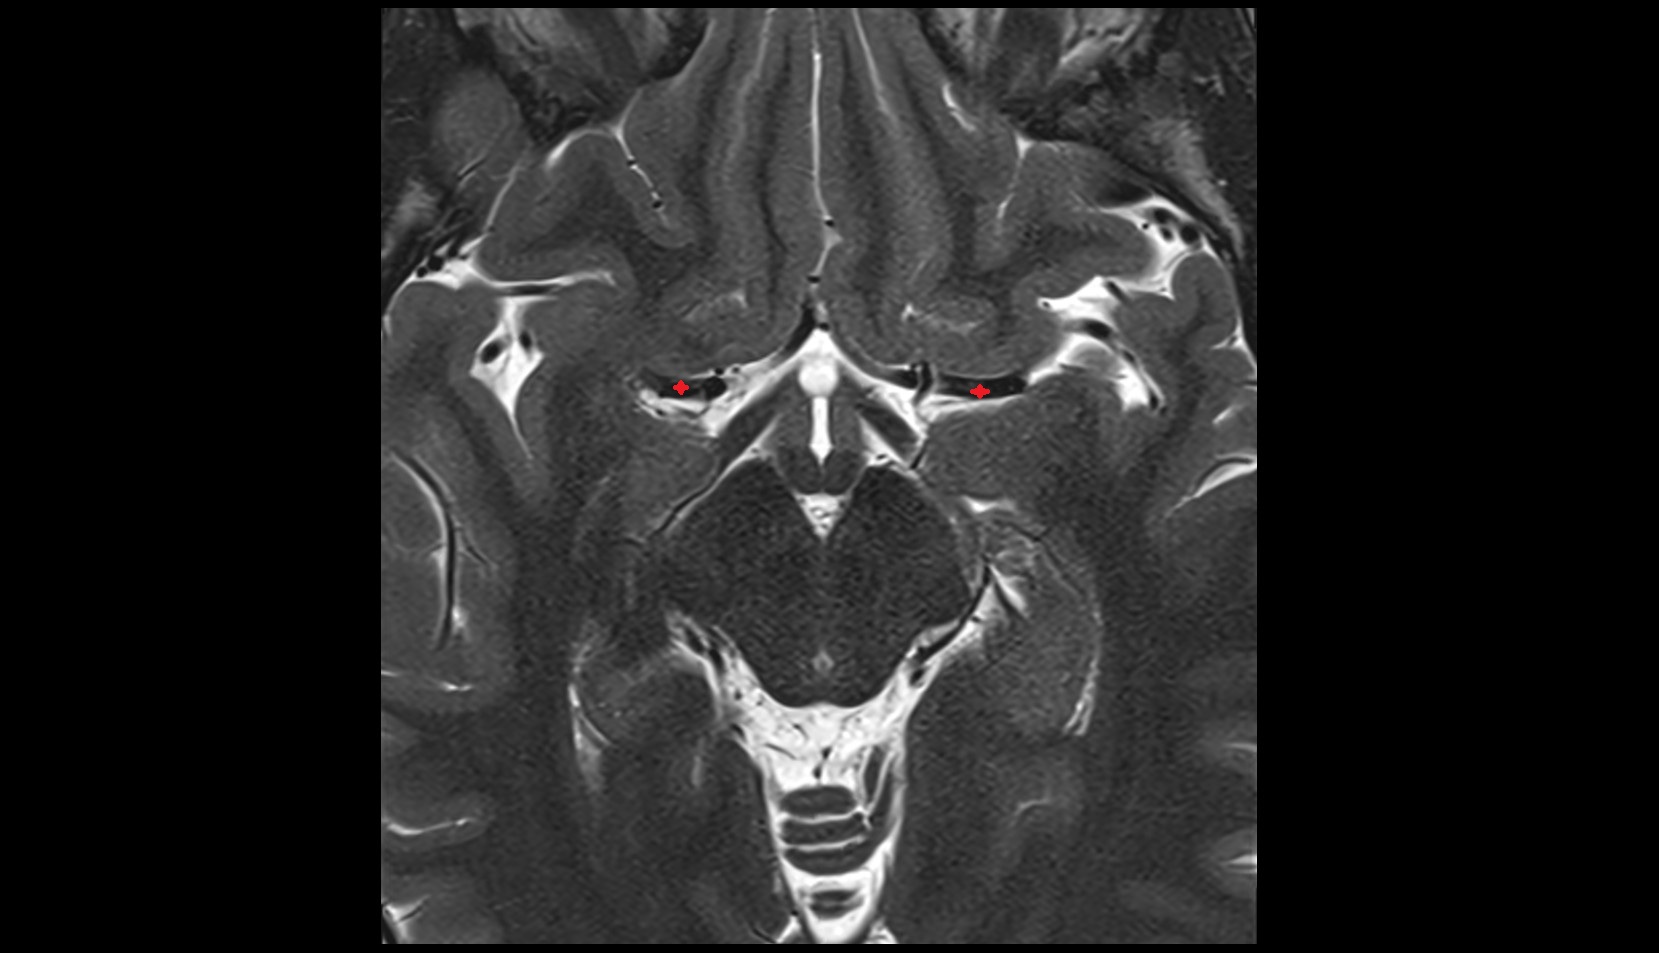

- Hippocampal body

- Hippocampal head

- Hippocampal tail

- Body of hippocampus

- Head of hippocampus

- Tail of hippocampus

- Hippocampus